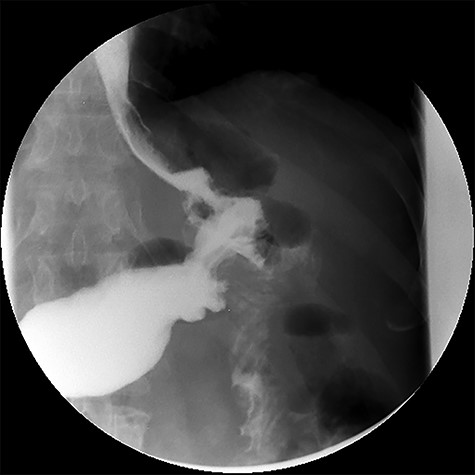

After treatment of the abdominal abscess with percutaneous drainage and antibiotics, an upper GI contrast swallow study confirmed persistency of the GGF without any spillage of contrast to the abdominal cavity (see Fig. 9). The patient was discharged, medicated with oral PPIs.

Upper gastrointestinal contrast swallow study image showing progression of contrast from the oesophagus to the gastric pouch and from the gastric pouch to the excluded stomach, confirming a gastro-gastric fistula.